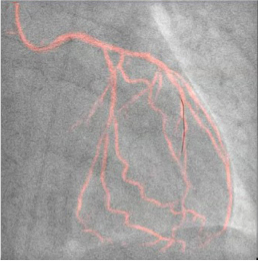

血管撮影装置をバージョンアップ

血管撮影装置をバージョンアップし、さらなる”被曝低減”と、一歩先の”治療支援システム”を実現。

当クリニックでは、現在稼働中の血管撮影装置2台のバージョンアップを行いました。

バイプレーン装置には、冠動脈疾病の血管内治療術を支援するライブイメージガイダンスの包括的システムソリューション”PCI Suite”を導入しました。

これまでは不可能であった治療中のライブ画像に血管の動画像をオーバーレイする機能(Dynamic Coronary Roadmap)や、また、高速画像強調処理技術によってステントの視認性をリアルタイムに向上させる機能(Live StentBoost)が加わり、新たな治療支援画像として威力を発揮しています。

また、iFR Roadmapは、Dynamic Coronary Roadmapの機能を強化し、複雑な狭窄病変の治療を、iFR値を参照しながら行えるシステムで、治療の必要な部位をより詳細に評価することができます。

一方、シングルプレーン装置では、より被曝低減が行えるArullaClarity FD10へバージョンアップしました。

我々は、これらの最新技術を地域の皆様に還元できるよう、今後も努力して参ります。

Dynamic Coronary Roadmap

Live StentBoost

iFR Roadmap